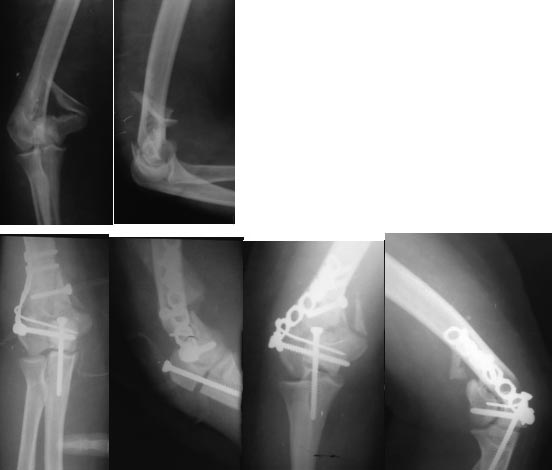

Из представленнего материала видно, что между снимками нет разницы. Отсутствует репозиция не только медиального, а также латерального мыщелка. На боковом снимке мыщелок расположен спереди, а прямом головка луча упирается в край мыщелка, что означает ротацию. Отсутствует компрессия между мыщелками, а один шуруп не смог удержать медиальную сторону, которая при первом же движении рассыпалось.

Ошибка в фиксации привела к дополнительным проблемам, теперь, кроме плеча, надо заниматься с локтевым отростком и невритом. Доступ обычно из двух сторон мышцы трицепса, но некоторым внутрисуставным переломам визуализацию можно создать за счет остеотомии локтевого отростка и как дружно заявили, что фиксацию заканчивает только по Веберу.

Технология не стоит на одном месте, и вместо спиц пришли менее раздражающие преконтурные пластины. Их можно уложить перед остеотомией, затем удаляют и сохраняют до конца операции вместе с шурупами. По окончании операции пластина укладывается на готовые дырки.

Прежде популярная фиксация шурупом сегодня уходит на второй план, хотя установку можно облегчить засчет предварительного проведения на всю длину до остеотомии. Обычный метчик и вместо 4.5 мм, более толстые 6.5 мм. Мелькие шурупы, попадая в центр канала, не удерживает ничего!

Разработаны различные концепции установки пластин на дистальное плечо: две параллельные в 180 или под углом в 90 градусов. Почти все компании имеют все варианты пластинок, а Acumed признает так называемую Keystone concept http://www.acumed.net/distal-humerus-plates

В данном случае надо делать ревизию. Среди остальных осложнении ложный сустав локтевого отростка лечить легко, фиксация пластиной и костный графт. Здесь в первую очередь надо создать конгруентость локтевого сустава и вместо толстых шурупов взять тонкие 2.5-3.5 мм. Это как раз случай, когда качество работы зависит не только от опыта хирурга, а и от наличия современного материала по рукой.

Примеры: первому более 15 лет фиксирован шурупом и tension band technique, а второй перелом открытый больной 80 лет, после наружного фиксатора в первом этапе и окончательная фиксация вторично. Третьий раз внесуставная остеотомия...